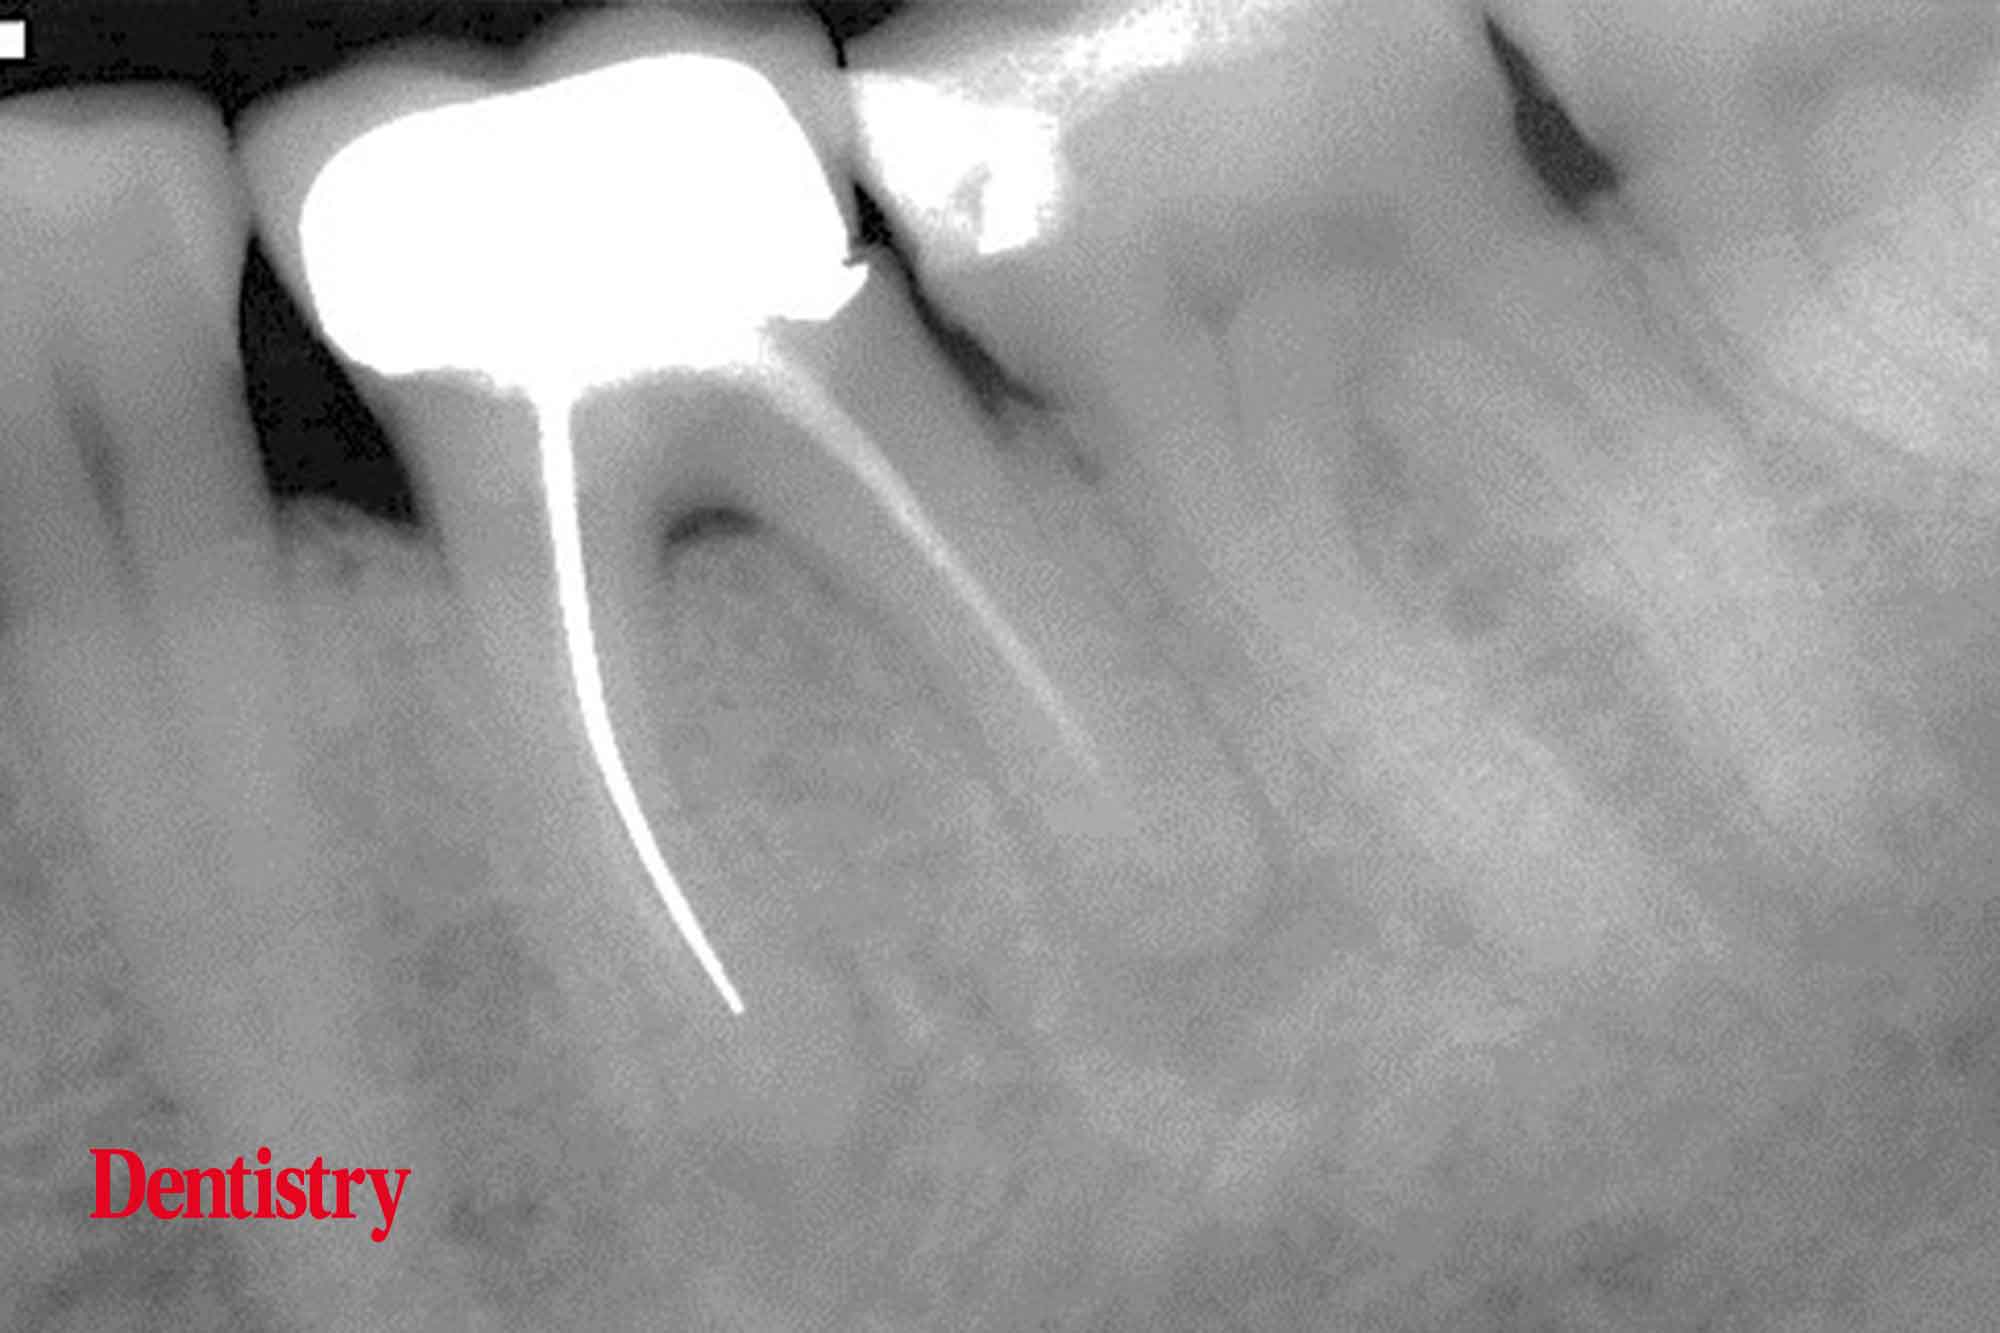

Exploring Endodontics a silver point of order Dentistry Silver Points In Endodontics Uses  Web  silver cones are no longer utilised for root canal obturation [ 9, 10 ]. Sargenti and richter proposed the principle of. Web silver points were historically indicated and well accepted as a root canal obturation material; Web silver points were historically indicated and well accepted as a root canal obturation material;. Web  apart from gp the alternate materials which. Silver Points In Endodontics Uses.

Exploring Endodontics a silver point of order Dentistry Silver Points In Endodontics Uses  Web  silver cones are no longer utilised for root canal obturation [ 9, 10 ]. Web radiographs show that silver points can be used satisfactorily in teeth that are to receive posts and root canal fillings may. Web clinicians frequently encounter endodontically treated teeth that contain silver points within their roots. Web  silver cones (also referred to as silver points). Silver Points In Endodontics Uses.